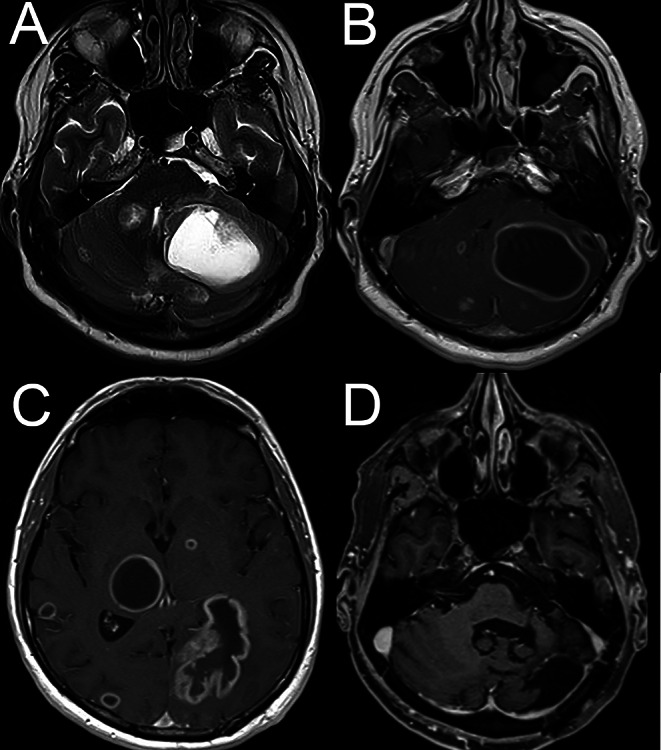

Case description: A 44-year-old male patient reported new-onset position-dependent vertigo with nausea and gait-imbalance for 10 days. During supine roll testing for the lateral semicircular canals, he showed a persistent apogeotropic PN (being more intense left-ear-down) accompanied by moderate vertigo. Except for the PN, the neurologic examination was normal. He received a diagnosis of a apogeotropic-variant right-lateral canal BPPV and responded well to a Gufoni maneuver (nose-up). However, on follow-up, apogeotropic PN showed-up again, converted into a geotropic variant after a Barbecue-liberation maneuver, and then disappeared. Due to the re-emergence of the initial PN on the second follow-up consult, a brain-MRI was requested, disclosing disseminated infra- and supratentorial cystic brain metastases. The largest mass compressed midline cerebellar structures. Urgent surgical resection revealed a histopathologic diagnosis of an adeno-carcinoma of the lung.